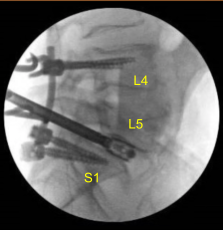

X-rays were repeated to confirm correct positioning and size. Neuromonitoring signals were stable. Next with the left L5 pedicle completely isolated and exposed, we placed left L5 pedicle screw decorticating with electric high-speed drill cannulating with the curved freehand Lenke pedicle finder palpating for breaches using 5.0 mm tap and placing 45 mm x 6.0 diameter titanium pedicle screw without difficulty.

We then similarly placed a right L5 pedicle screw as well using similar technique. We draped the patient sterilely and obtained an intraoperative CT scan which showed correct positioning of all the pedicle screws and interbody spacer.

Precut and precontoured titanium rods were selected and placed across the tulips and secured with locking caps, which were all final tightened with torquing and anti-torque devices at L4, L5 and S1. Morselized demineralized bone matrix autograft collected from the decompression as well as bone morphogenic protein allograft were packed into the lateral gutters from L4 to S1 to the posterolateral arthrodesis.

We took final AP and lateral x-rays, which showed correct positioning of all the hardware. The closure will be dictated separately. At the end of the case, the patient was turned supine on the cart, and transported to the recovery room in stable condition.

The patient followed up 10 weeks after the surgery for a routine postoperative visit with no complications or signs of infection. Since then the patient has been able to return to their daily activities. Severe radiculopathy and back pain has improved along with no more foot drop syndrome observed.